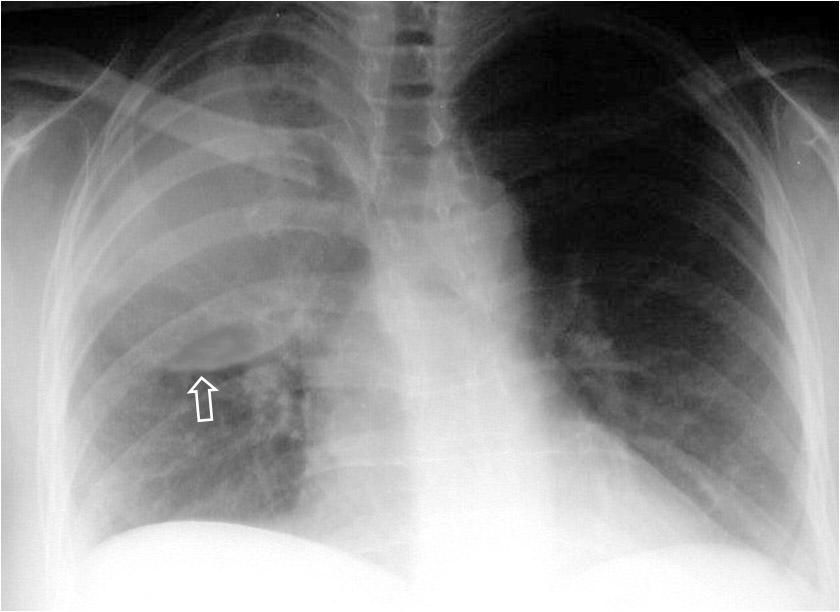

SIGNO DE LA CISURA ABOMBADA O DE LA HINCHAZÓN DEL LÓBULO

Este es un signo poco útil en la actualidad. Es visible en la radiografía de frente de tórax y se presenta como una condensación alveolar que se asocia a un abombamiento inferior de la cisura adyacente (flecha). Este signo, descrito inicialmente como característico de la neumonía por Klebsiella (neumonía de Friedlander), ha sido visto en otras entidades: neumonía por neumococo, H. influenzae, tuberculosis, absceso, neumonitis obstructiva, e incluso en el carcinoma bronquioalveolar.